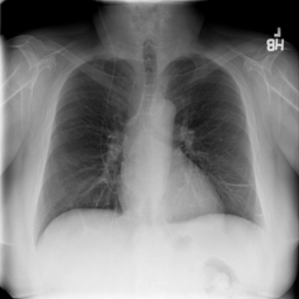

4.1 Qualitative Evaluation of Healthy Counterpart Generation

Example images from the disease COVID-19 Radiography Database and their generative healthy counterparts are given in figure 2. The images on the far left are instances of the lung opacity class from the real images in the dataset. The images in the middle column are examples of the generated healthy counterfactuals obtained via latent space diffusion, with RadBERT-guided textual-conditioning via a conditional prompt “normal chest x-ray”. A total of 75 diffusion inference steps are used with image conditioning strength=0.85 and guidance scale=7.5. (The former indicates the level of constraint on changes to the original input image and the latter is the weight given to the textual encoder conditioning in the generation of the image, ranging over [0,1] and [0,9], respectively).

Side-by-side inspection of the generated healthy counterfactuals (as per fig. 2) suggests that, as required, only minimal perturbation is made to the original image with respect to healthy pixels -i.e. localized image sites without structural medical defects. (In the top row, the medical structural defect in the original image is due to a lung opacity, and characterized via a relatively complex interaction between the imaging modality and subject manifesting as ‘gaps’ in the corresponding portions of the lung scan). The healthy/non-healthy discrepancy maps in all of these cases are obtained via masked subtraction of the original image from the generated image (the ground truth segmentation masks correspond to the broad area of interest –i.e. the complete lung). The generated healthy tissue is thus a subset of the mask and is shown in the final column of fig. 2 for the respective cases.

In the context of a VANT-GAN[20]-based approach, this highlighted material constitutes the diagnostic counterfactual visual attribution, i.e. the selection of material relevant to the diagnosis of the unhealthy condition. Healthy counterfactual generation was performed for the complete datasets in the three unhealthy classes, i.e Lung opacity, Viral Pneumonia and COVID, examples of which are given in fig. 3 for the three classes (all of the generated healthy counterfactuals from this experiment can be found on https://huggingface.co/ammaradeel/diffusionVA). Visual inspection indicates that the generated counterfactuals are, in general, visually plausible with minimal perturbation made to the unhealthy image overall. Moreover, the healthy counterpart generation does not appear to unnecessarily affect aspects of the images unrelated to the medical condition, the model selectively making changes to the unhealthy regions in a structurally plausible manner, e.g. generating missing portions of the lung without generating extraneous lung material where it would be expected to normally exist (e.g. in the abdominal cavity).